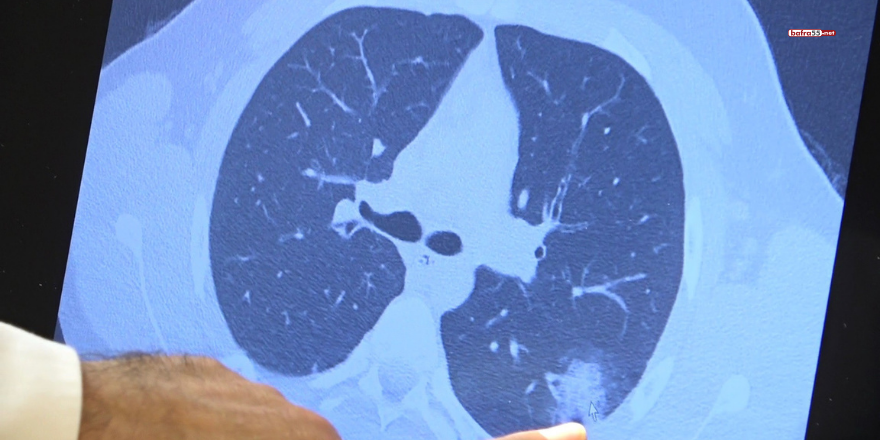

Bazı vatandaşlar hâlâ aşı olmakta tereddüt etmeye devam ederken korona virüs çocuk grubundaki hastaları da etkilemeye başladı. Prof. Dr. Şevket Özkaya ise aşı olabilecek yaş grubundaki çocukların bir an önce aşılanması gerektiğine vurgu yaptı. 14 yaşında, kronik rahatsızlığı olan ve akciğerlerinde tahribattan dolayı ciddi öksürük, ateş ve nefes darlığı çeken bir hastanın akciğerlerini inceleyen Prof. Dr. Özkaya, "14 yaşındaki kronik rahatsızlığı mevcut olan bir genç hastamızda ciddi akciğer tutulumları var. Her iki akciğerinde de yaygın buzlu cam ve konsolidasyon alanları var. Bu yaştaki çocuklarda beklemediğimiz bir durumdur. Okullarımızda da bu risk var. Okullarımızın açık kalmasının ve sağlık sistemimizin kitlenmemesi için mutlaka aşı olmalıyız. Çocuklarımıza rol model olmalıyız. Şu anda hastanelerimiz hastalara yetişebiliyor. Yatak sayımız yeterli. Ancak kontrollü sosyal hayatımızı düzene sokmadıkça ve aşı olmadıkça, gelecekte hastanelerde yatak sayısı sıkıntısı çekebiliriz" dedi.